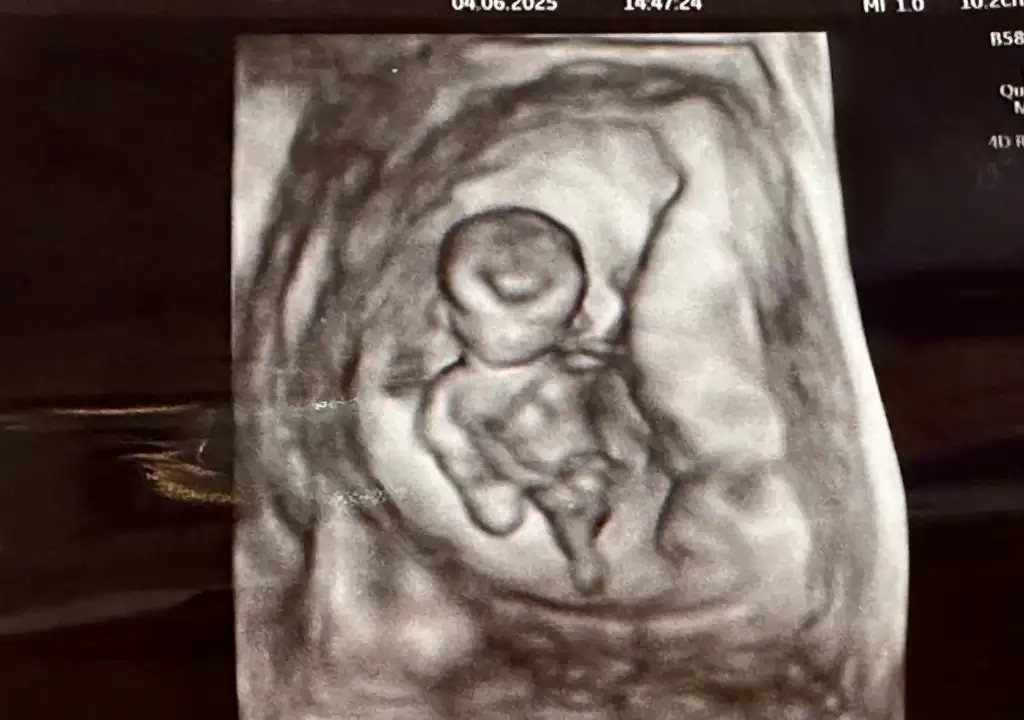

Erkek benceBize de bakar mısınız13 haftalık olduk

Bize de bakar mısınız13 haftalık olduk

Sol tarafta üç çizgi mi gördünüz, ben öyle görüyorum sankiiBana kız gibi geldi sağlıkla doğsun inşallah

Bana da bakarmısınız acaba? 16hafta ama belirsizilk fotoda kız gördüm 3 çizgi gibi 3. fotodada pipi gördüm :)